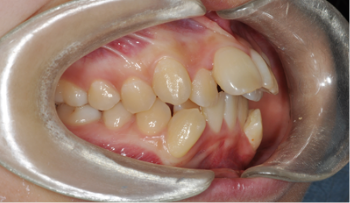

자료 채득

X-ray, 구강 내ㆍ외 카메라 사진, 치아 모형, 턱관절 및 치주 상태,